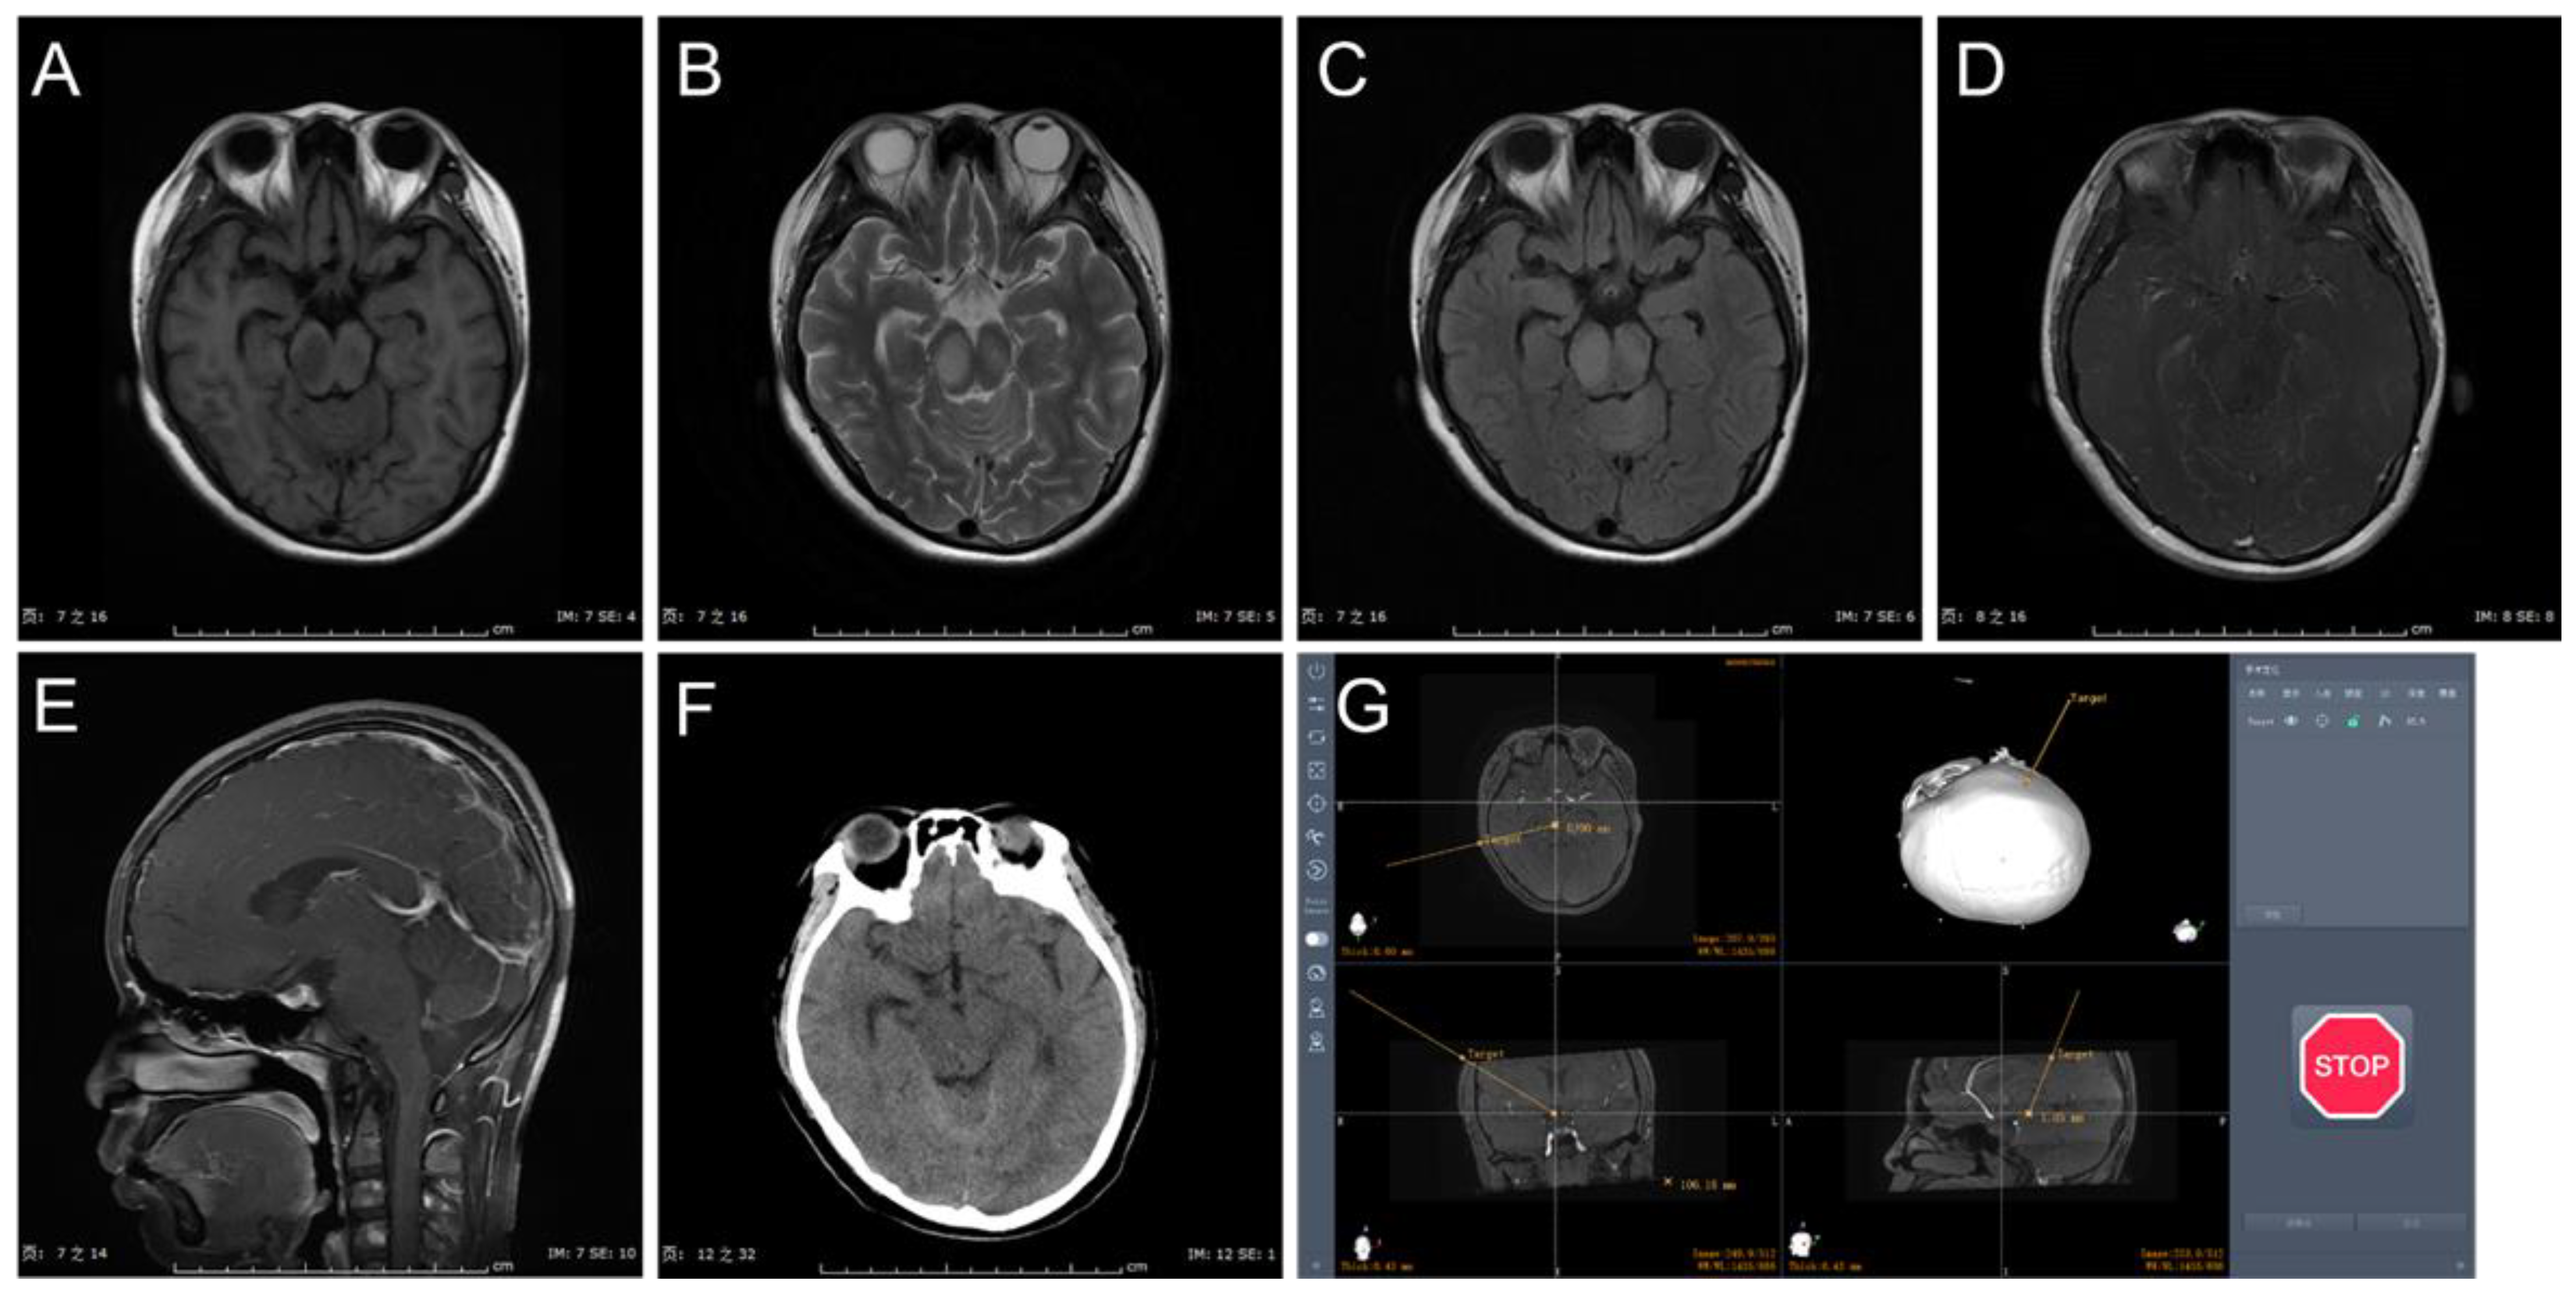

2.2. Surgical Procedure